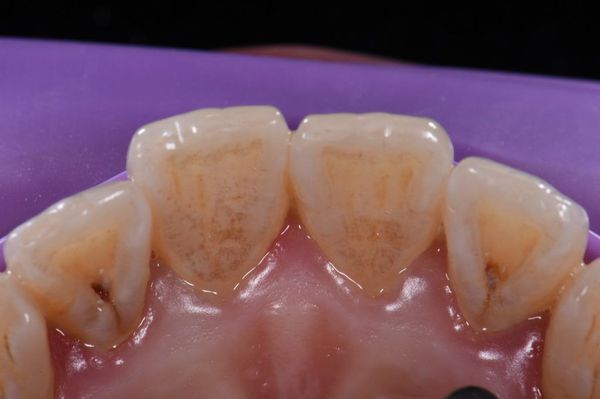

Zęby z ewaginacją szkliwa (ewaginacją zęba, dental evagination) charakteryzują się obecnością dodatkowego guzka, na którego powierzchni często występują głębokie bruzdy (szczeliny, fissurae). W tych zagłębieniach łatwo gromadzi się płytka nazębna i resztki pokarmowe, co sprzyja rozwojowi próchnicy (caries dentium) oraz zapaleniu dziąseł. Z tego powodu zęby z ewagynacją wymagają szczególnie dokładnej higieny oraz regularnego nadzoru stomatologicznego.

Inwaginacja zęba (dens invaginatus) i ewaginacja zęba (evaginatio dentis) nie tylko pogarszają estetykę, ale też zwiększają ryzyko gromadzenia się płytki nazębnej i resztek pokarmowych, co sprzyja rozwojowi próchnicy (caries dentium). Dodatkowo ewaginacja może powodować urazy języka podczas żucia lub mówienia. W niektórych przypadkach prowadzi także do bólu w obrębie stawu skroniowo-żuchwowego (staw skroniowo-żuchwowy, TMJ) z powodu nadmiernego nacisku i przeciążenia wystającego guzka.

Próchnica w zębach z inwaginacją